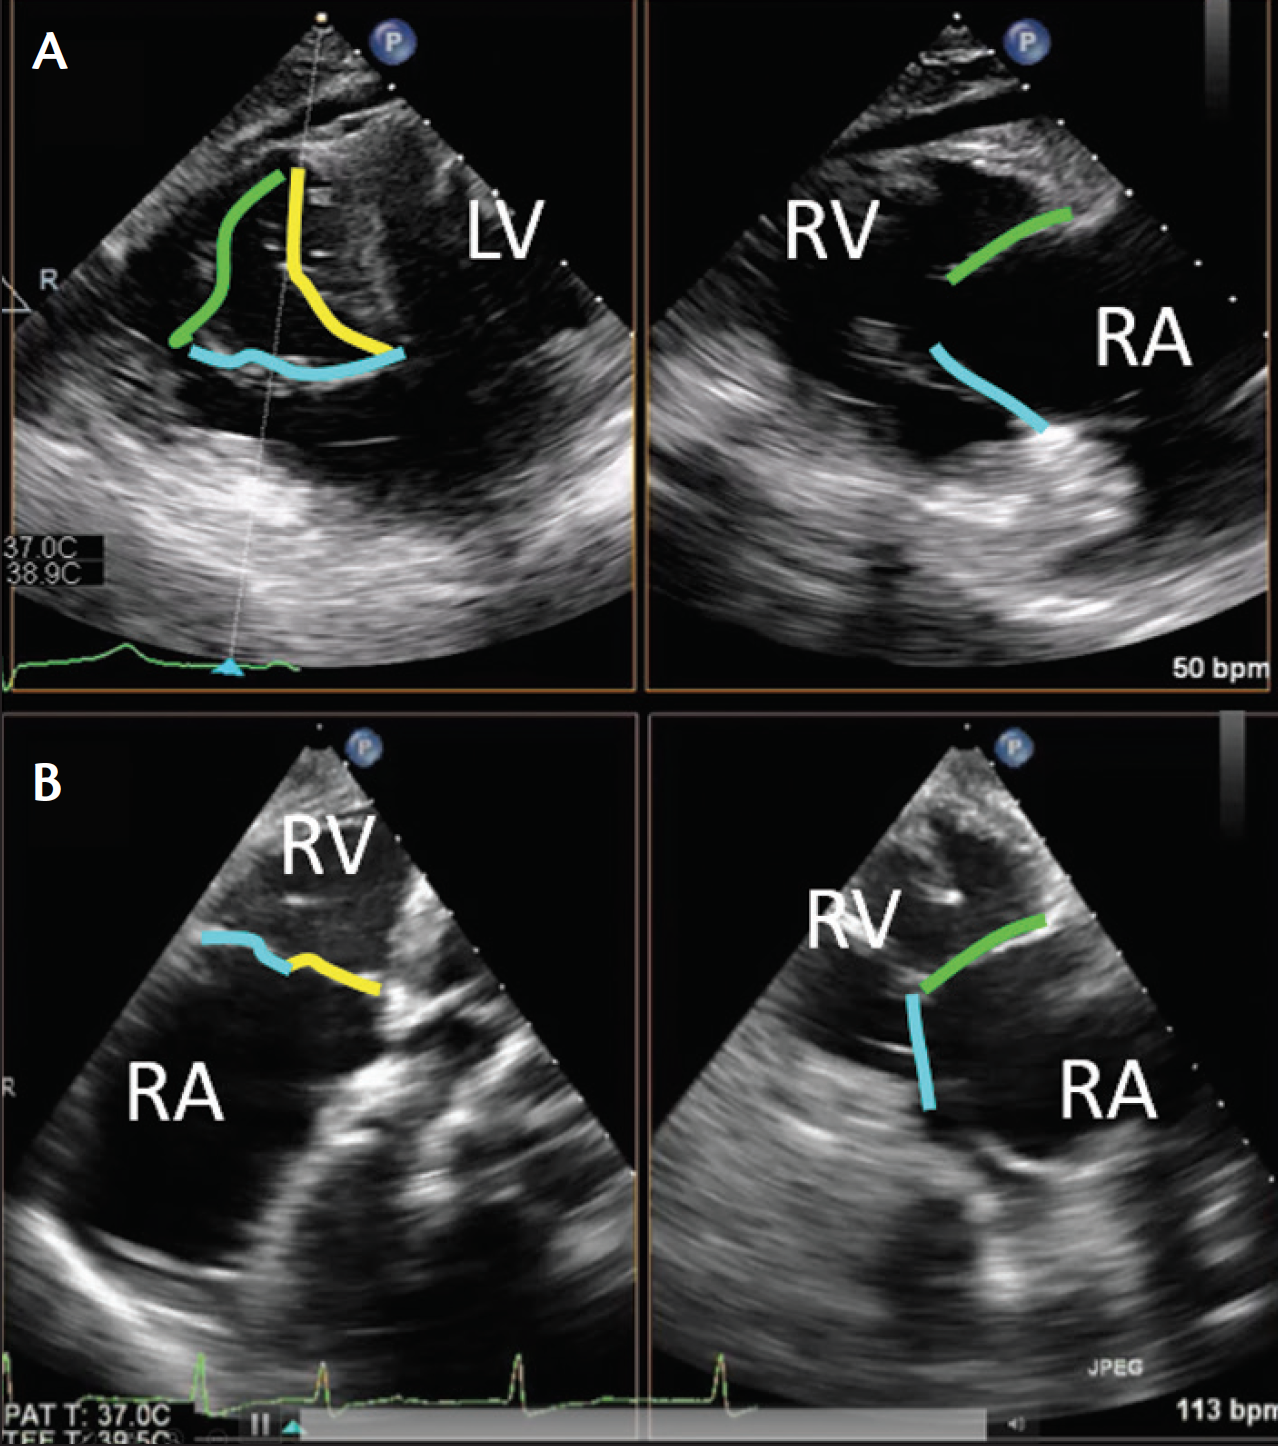

Figure 3. Mid-esophageal biplane imaging of the tricuspid valve. The 60° to 90° view typically allows imaging of the anterior (adjacent to the aorta) and posterior leaflets. Using simultaneous multiplane imaging from this primary view will then permit imaging of anterior-septal coaptation (A), as well as posterior-septal coaptation (B). Note: the color code for tricuspid leaflets is the same as in Figure 2. Abbreviations: AV, aortic valve; RA, right atrium; RV, right ventricle.

The midesophageal inflow-outflow view at approximately 60° images the anterior leaflet (adjacent to the aorta) and the opposing posterior leaflet (Figure 3). From this imaging plane, the septal leaflet is typically only imaged using simultaneous biplane views. An orthogonal imaging plane adjacent to the aorta (Figure 3A) will image septal-anterior coaptation. Moving the orthogonal image away from the aorta (Figure 3B) will image the septal-posterior coaptation. Because the lower right heart border is close to the diaphragm, slow insertion brings the TEE probe to the distal esophagus just proximal to the gastroesophageal junction; there may be no view of the left atrium proximal to the tricuspid valve in this imaging plane, only the right atrium and coronary sinus (Figure 4A). As this view of the tricuspid valve is unobstructed by left heart structures, it is ideal for performing a comprehensive evaluation of tricuspid valve function and for acquiring 3D volumes of the tricuspid valve (Figure 4B and Figure 4C).

Figure 5. Transgastric views of the tricuspid valve. Advancing the TEE probe into the stomach results in the shallow (A) and deep (B) transgastric views. From the shallow transgastric level, a short-axis view of all three tricuspid valve leaflets is possible, which helps identify catheter positions relative to the leaflets/annulus. Advancing the TEE probe further into the stomach, along with rightward anterior flexion, produces a deep transgastric view of the tricuspid valve and aligns flow across the valve for Doppler assessment of regurgitant severity, as well as spectral Doppler evaluation of the TR jets. Note: the color code for tricuspid leaflets is the same as in Figure 2. Abbreviations: LV, left ventricle; RA, right atrium; RV, right ventricle.

Advancing the TEE probe into the stomach results in transgastric views (Figure 5). At 0°, rightward anterior flexion will result in the inflow-outflow view, again with imaging of the anterior (adjacent to the aorta) and posterior (adjacent to the diaphragm) leaflets. Rotating the multiangle probe to 60° to 90° results in the only 2D view that provides simultaneous visualization of all three tricuspid valve leaflets with the posterior leaflet in the near field, the anterior leaflet in far field, and the septal leaflet adjacent to the septum (Figure 5A). Advancing the TEE probe further into the stomach along with rightward anterior flexion produces a deep transgastric view of the tricuspid valve (Figure 5B), which also permits optimal color flow and spectral Doppler evaluation of TR jets.